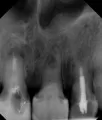

В шестом зубе на корнях хроническое воспаление, которое периодически обостряется. Можно попробовать пролечить каналы и посмотреть, как будет зуб себя вести, но не факт, что их удастся пройти и качественно пролечить.

В седьмом зубе, на переднем корне, есть перфорация, выведен пломбировочный материал в периапикальное пространство (околокорневое), отсюда боли и дискомфорт. Качественно и надёжно пролечить этот зуб не получится. Вы можете отдать много денег и времени, а соответствующего результата не получите. Удаление, а в дальнейшем имплантация.